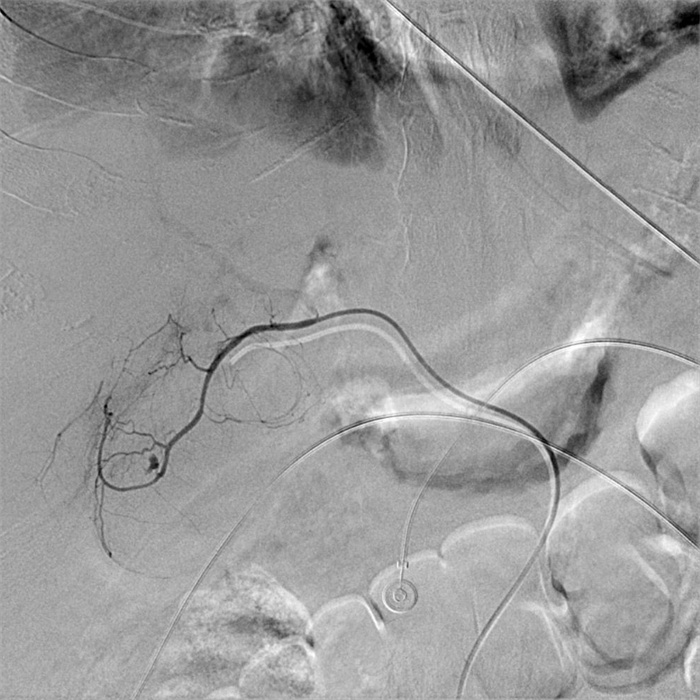

入院第57天,患者再次出现暗红色血便,伴阵发性右上腹痛,无发热、呕血,症状与之前相同。鉴于患者有活动性出血,再次复查胃镜:慢性浅表性胃炎伴糜烂。复查肝功能:γ-GT 844 U/L,TBil 43.6 μmol/L,NCBil 16.6 μmol/L,CBil 27 μmol/L,肝功指标再次回升,γ-GT、CBil明显升高,提示可能出现胆道梗阻。肝胆脾胰腺彩超复查:胆囊肿大、胆囊陈旧性稠厚淤胆(较前无明显变化),胰腺稍大并不均质改变。复查上腹CT:AP复查情况与之前相同,可能有胆囊出血(见图 2)。联合介入放射科行血管造影检查,常规局部麻醉下采用Seldinger技术由右侧股动脉入路,造影发现胆囊动脉分支出血(图 3),超选择胆囊动脉分支用明胶海绵颗粒行栓塞止血(图 4)。同时,行经皮经肝胆囊穿刺置管引流(图 5),病情稳定后带管出院,3月后予以拔除,择期行胆囊切除。

| 胆囊动脉增粗,其分支局部造影剂外溢,未见明显动脉瘤征象 图 3 胆囊动脉造影 |

回顾总结该病例,不难发现,患者病程中两次活动性出血有共同点:先间断性右上腹痛,继之便血,伴γ-GT、CBil指标异常升高,以及胆囊内出现疑似结石、出血的影像学改变。胆囊内出血经胆道排出后,在十二指肠处可见少量新鲜血液,故首次胃镜检查时,根据十二指肠球部少量新鲜血迹判断球部炎症存在一定的误诊。另外,特别需要强调的是,少量的出血混合胆汁在影像学检查上表现为疑似新发的胆囊结石,临床不应直接考虑为胆囊淤胆性结石,尤其急性SAP患者出现上诉临床特征时,应当考虑胆囊动脉出血的可能性。直至患者第二次便血后,再次组织多学科会诊联合介入放射科进一步行血管造影,发现并确定胆囊动脉出血,但未见明显动脉瘤征象,行胆囊动脉栓塞后患者出血停止。

胆囊动脉出血是罕见的胰腺炎血管并发症,确切的病理基础尚不清楚,推测其出血的机制主要继发于胰管释放的胰酶侵蚀及炎症刺激损伤血管壁[4]。介入放射科的共同参与在复杂胰腺炎的救治中有着重要作用[8],胆囊动脉出血难以被常规的检查发现,尤其是经常规治疗后患者仍有活动性出血时,选择性血管造影应作为首选方法。血管造影仍然是目前判断有无活动性出血的“金标准”,敏感度可达80%~90%以上[9]。血管造影同时发现异常血管、急性出血病因及部位[10],发现病灶的同时可给予介入治疗,有助于迅速维持血流动力学稳定。